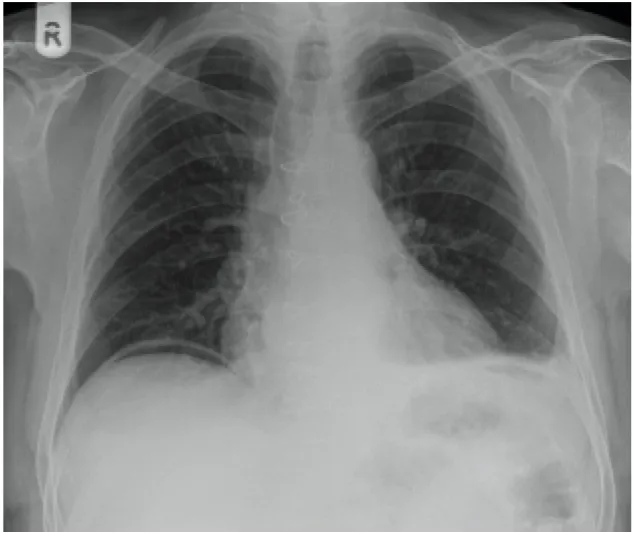

48세 남성이 3 시간 전에 시작된 심한 복통을 호소하며 내원했다. 환자는 복부 전체에 걸쳐 압통을 보이며 복부 근육의 경직을 나타냈다. 가슴 X-ray 사진이다. 이 환자에게 필요한 처치는 무엇인가?

• 심한 복통을 호소하는 환자에서 복부 경직이 나타나고 있다.

• 가슴 X-선에서 복강 내 free air가 관찰되는데, 심한 복통이 동반될 경우 이는 위장관 천공을 시사한다.

• 따라서 즉시 응급개복술이 필요하다.